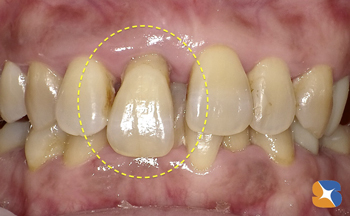

〈治療前〉

前歯が垂れ下がり、見た目も良くないので先ず、歯から神経を抜き取る治療にとりかかる。